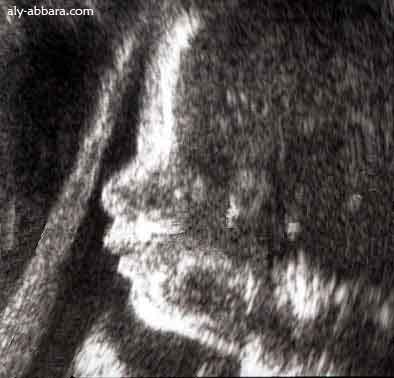

Profil

Quand l'imagerie médicale devient de l'art plastique

Auto-Diaporama d'une image échgraphique subissant de multiples modifications la transformant en images d'Art plastique

Il s'agit d'une image échographique composée puis traitée, animée et publiées par Dr Aly Abbara